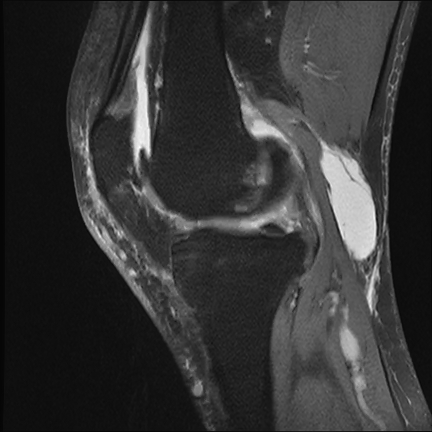

术前核磁共振提示腘窝巨大囊肿

膝关节外侧半月板损伤(III°)